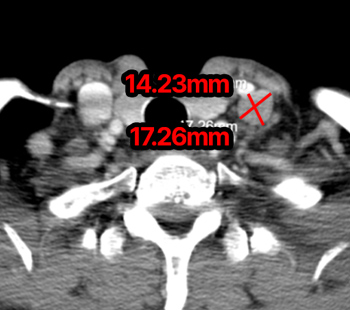

2025.1.16 CT

2025.4.9 CT

※ 동일한 조건에서 촬영된(사진에 대한 별도 조작이 처리되지 않은) 본원에서 진료 및 치료를 받으신 고객(들)의 사진입니다.

사진의 결과는 사례에 기반한 참고 자료로, 개인별 치료 결과는 상이할 수 있습니다.